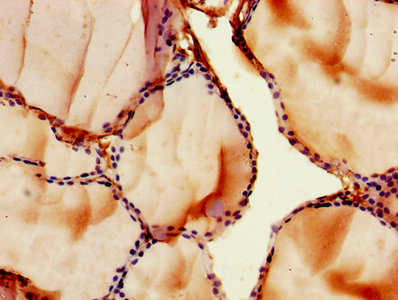

IHC image of CSB-PA009112LA01HU diluted at 1:500 and staining in paraffin-embedded human thyroid tissue performed on a Leica BondTM system. After dewaxing and hydration, antigen retrieval was mediated by high pressure in a citrate buffer (pH 6.0). Section was blocked with 10% normal goat serum 30min at RT. Then primary antibody (1% BSA) was incubated at 4°C overnight. The primary is detected by a biotinylated secondary antibody and visualized using an HRP conjugated SP system.